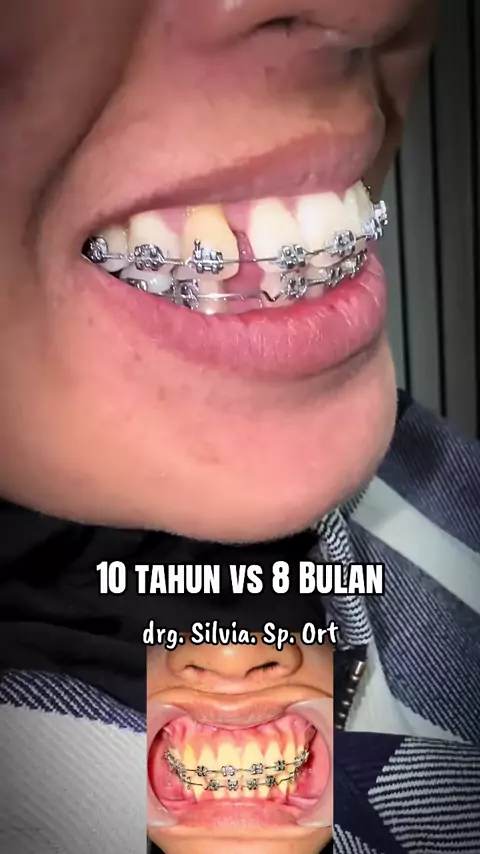

Risk it All... Risk all the cases Brain training Thinking Put it on Move it slowly With my mind and heart Still 3 times Need more but wish not that long Ambil Risiko Semuanya... Ambil risiko semua kasus Latihan otak Berpikir Insersi Gerakkan perlahan Dengan pikiran dan hatiku Masih 3 kali Butuh lebih banyak tapi berharap tidak lama lama I Wish I Pray Good night 🌹 Swet Dream drg. Silvia. Sp. Ort#behel#behelgigi#progress#orthodontist#

HARI INI (Kontrol Ke 4 ) Maloklusi kelas 1, gigi atas dan bawah berdesakan. Pergerakan pelan pelan saja dan semakin indah dalam 5 bulan, tidak terlalu lama. Masih perlu beberapa perawatan, tetapi kemajuannya nyata, perlu menemukan kunci oklusi di bagian posterior kanan. Rotasi gigi dan gigi yang berdesakan telah terkoreksi dengan baik. Alhamdulillah Y Rabb Semua ini karena tuntunanmu semata di pikiran dan hatiku, selama seluruh perawatan dan perjalanan pemasangan behel. Allah Maha Besar, Mah...